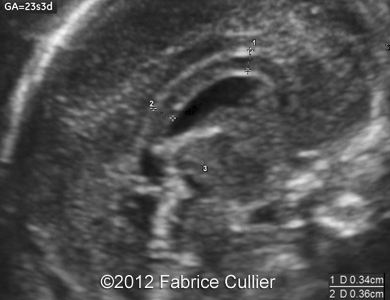

Image 3, 4, 5: An abnormally thick corpus callosum.

1C

1D

1F